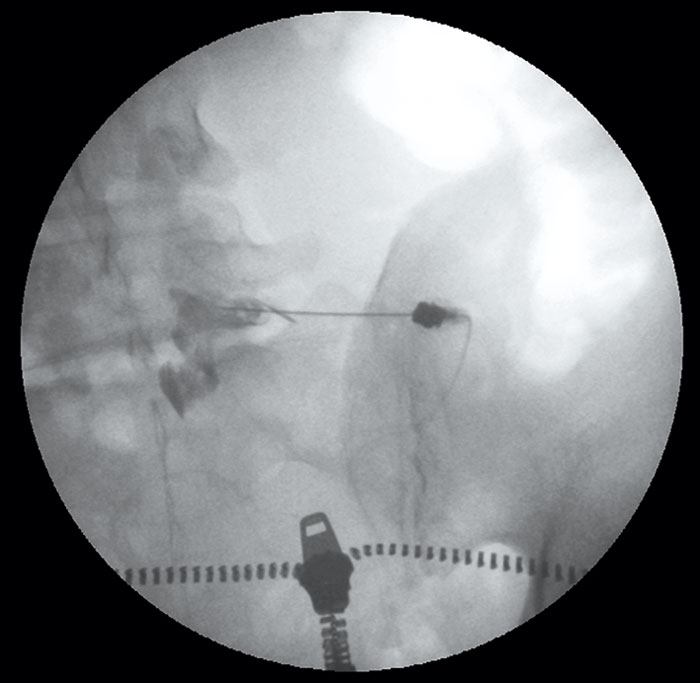

• Vid transforaminala injektioner ställs högre krav. Där räcker det inte med röntgenkontroll av nålens läge. Man måste även injicera kontrast under röntgenkontroll i realtid, och helst med subtraktionsteknik, för att försäkra sig om att man inte ligger i ett blodkärl (Figur 4). Förlängningsslang mellan nål och spruta ska användas för att inte riskera rubba nålläget när man injicerar. Enbart fullt lösta steroider typ dexametason ska användas.

Figur 4. Röntgenkontroll vid transforaminal injektion.